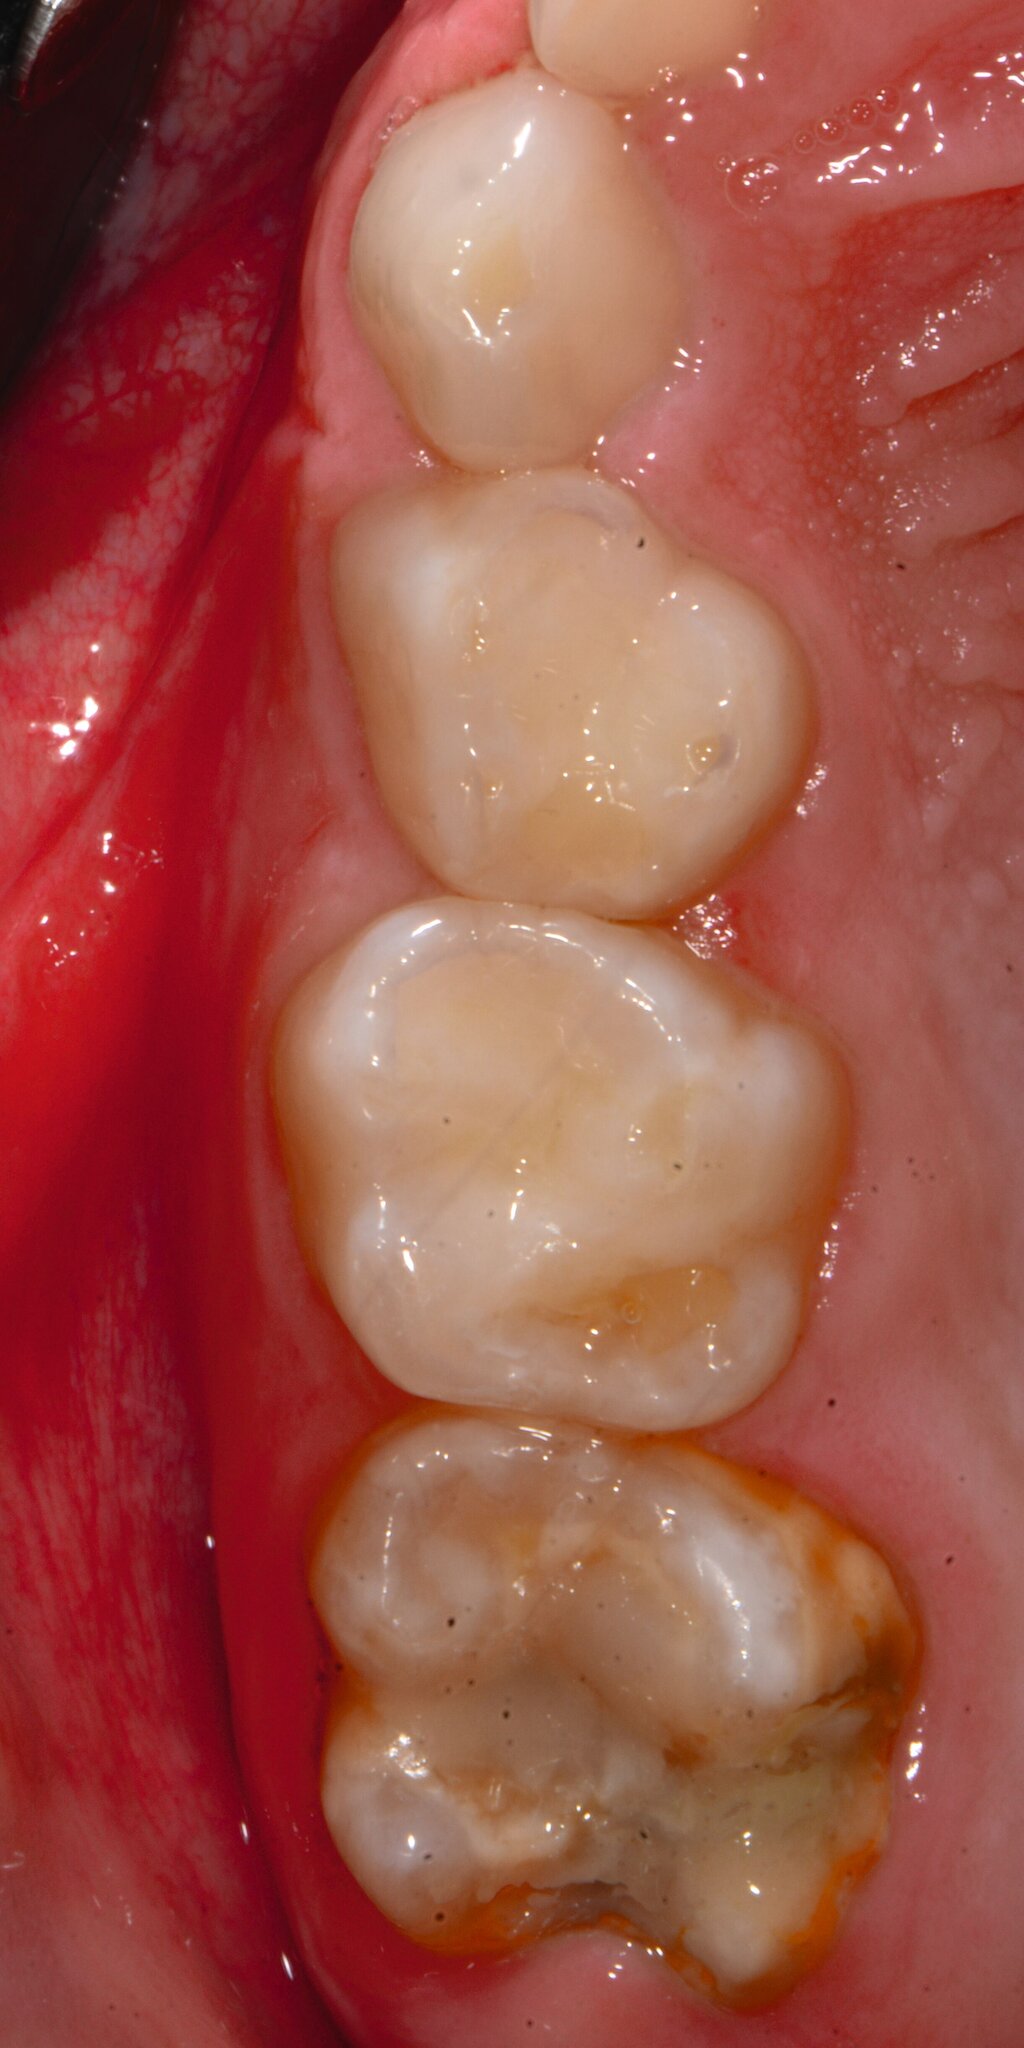

Das klinische Erscheinungsbild an bleibenden Zähnen zeigt typischerweise weißlich-gelbe bis gelblich-braune Opazitäten, die zumindest in einigen Bereichen durch eine scharfe Abgrenzung (engl.:„demarcated opacities“) zum gesunden Zahnschmelz charakterisiert sind (Abbildungen 3 und 4). Die abgegrenzten Hypomineralisationen befinden sich mehrheitlich im Bereich der inzisalen Kronenhälfte unabhängig von dem Auftreten an Front- oder Seitenzähnen. Die Ausprägung am Zahn kann dabei auf einzelne Areale oder Höcker begrenzt sein.

Bei einer schwerwiegenderen Ausprägung sind Zahnflächen vollständig betroffen, mitunter alle Zahnflächen an einem Zahn. Die Verteilung in der Dentition beziehungsweise an den Indexzähnen ist gleichermaßen variabel und betrifft nicht nur die Defektgröße, sondern auch die Farbe und Festigkeit. Was die Festigkeit betrifft, gilt als die Faustregel: Je dunkler die Farbe des Schmelzes, umso weicher beziehungsweise poröser und damit minderwertiger wird dessen Qualität sein. Damit reduziert sich seine kaufunktionelle Belastungsfähigkeit, was insbesondere an ersten bleibenden Molaren von klinischer Relevanz ist.

An umfangreich hypomineralisierten Zähnen können Schmelzeinbrüche (engl.: „enamel breakdown“ oder „enamel desintegration“, Abbildung 5) auftreten [Lygidakis et al., 2010; 2022]. Da diese oftmals die Folge einer fehlenden Belastungsfähigkeit des Zahnschmelzes sind und erst nach der Einstellung der Zähne in die Okklusion auftreten, werden sie auch als posteruptive Schmelzeinbrüche bezeichnet. Sie sind häufig im Bereich der Kauflächen beziehungsweise Höcker der Molaren zu finden, führen zur Dentinexposition und damit einhergehend zu ausgeprägten Hypersensitiven insbesondere bei Kindern, deren Zähne gerade erst durchgebrochen sind [Linner et al., 2021].